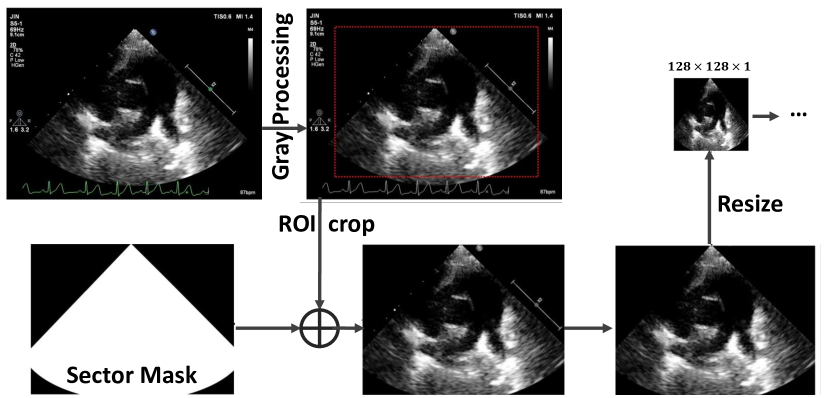

Refer to caption

Figure 3: Data pre-processing flowchart.

Pre-processing

The selected color key frames were first translated to the gray images, since the echocardiogram region has only single-channel 2 gray value information. Then, we cropped the region of interest (ROI) with a redefined sector mask. Since a typical input to convolutional neural networks (CNNs) has the size of 128×\times128, we resized the masked ROI to the 128×\times128 image. The five views were stacked following a specific sequence (i.e., SLAX, PSSAX, A4C, SXLAX, and SSLAX) to form our five channels training sample.